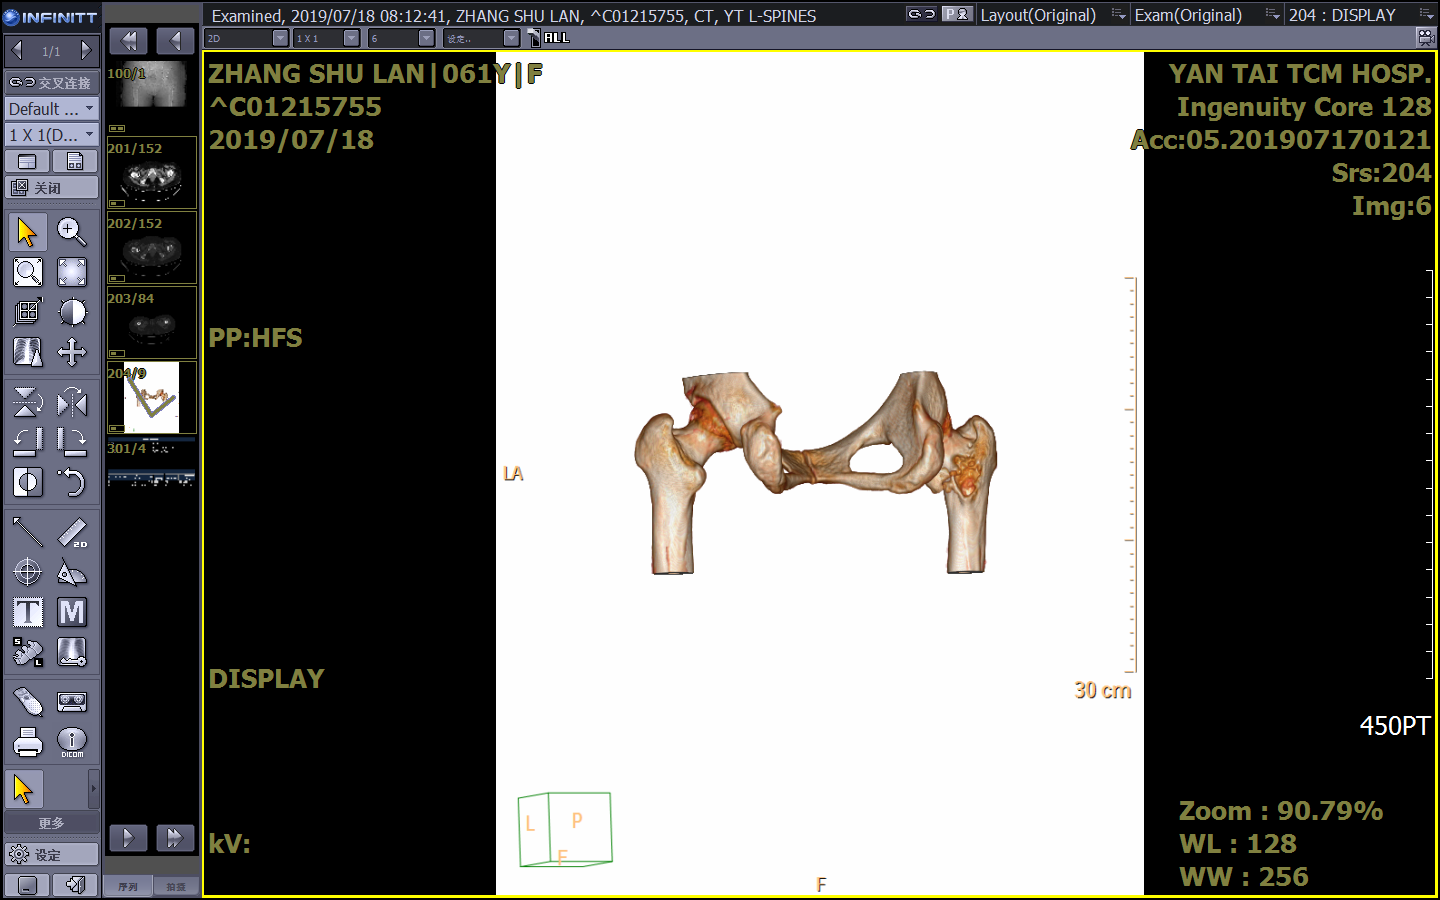

PET-CT示:1.腰3椎體(tǐ)局限性骨質破壞,FDG代謝輕度增高;股骨頸局限性骨質破壞,周圍軟組織受侵、腫脹,局部條狀骨骼密度影(yǐng),FDG代謝增高。右側顱骨及腰椎多個椎體(tǐ)骨質破壞、胸椎多個椎體(tǐ)低密度影(yǐng),FDG代謝不高。考慮骨髓瘤?

因患者存在椎體(tǐ)及股骨頸骨損,患者目前隻能扶杖行走,爲了能夠更好地改善患者生(shēng)活質量,預防病理性骨折發生(shēng),需要對如(rú)下骨損進行外科幹預治療。

針對多發性骨髓瘤患者的椎體(tǐ)及髋關節骨質破壞情況,各科室主任、骨幹紛紛提出積極下一步治療手段,最後經過多學科討(tǎo)論,主要可(kě)選擇的治療手段有:行髓内釘固定、骨水泥固定、腫瘤侵蝕區域的放(fàng)射性粒子植入治療、換髋關節等方法。具體(tǐ)選項要根據患者的實際情況及經濟狀況和家屬商量決定。